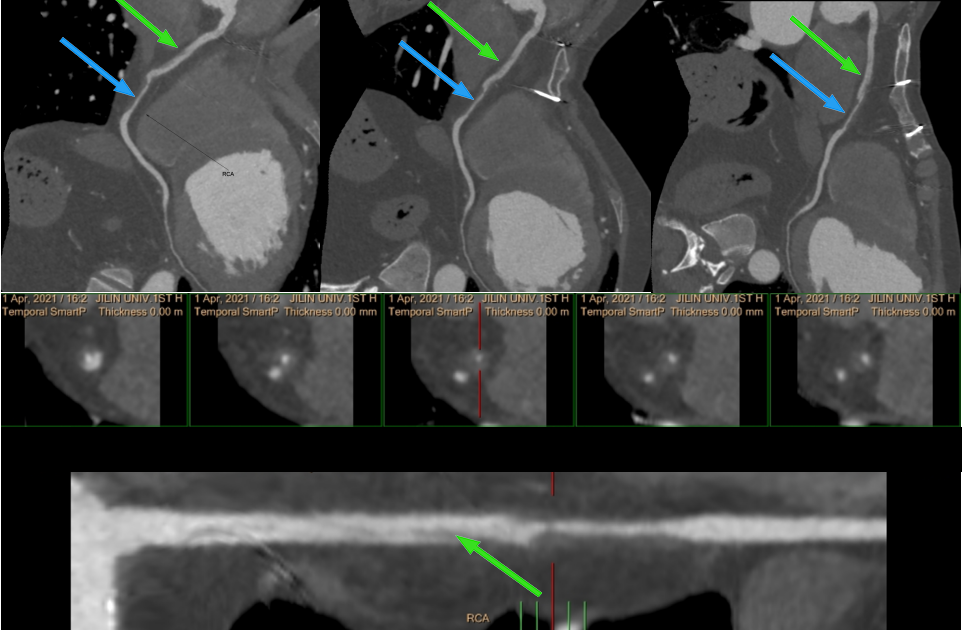

冠脉 CTA:

右冠状动脉近段双腔影,中段偏心性低密度,管腔中度狭窄。

1、考虑右冠状动脉近段夹层;右冠状动脉近中段偏心性低密度影,考虑壁间血肿,估计管腔重度狭窄

2、左冠状动脉前降支中段(近第二对角支分叉处)限局性夹层

本例即为右冠状动脉近段 TYPE1 型,中段 TYPE2B 型;左冠状动脉前降支 TYPE1 型